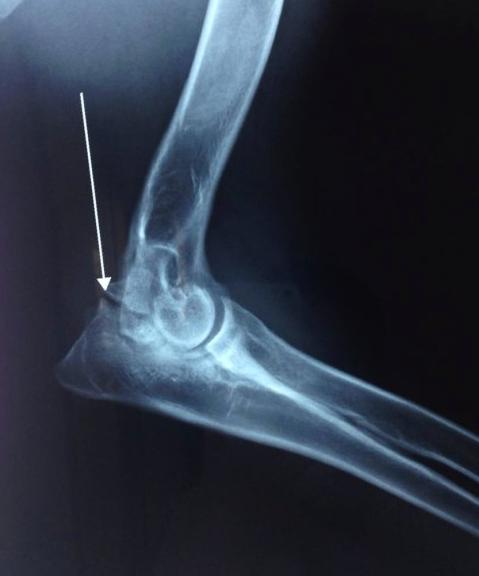

关节软骨无法在特定位置转变为骨骼,直接令到这区域的软骨增厚,增厚的软骨与周围正常的软骨分离形成了皮瓣,这一系列过程便称之为OCD。异常软骨的皮瓣有可能会发生从关节表面脱离,形成“关节鼠”。

图为“关节鼠”

那么,什么是“关节鼠”?

这一术语较好理解,意指关节出现病变的时候,在关节软骨内部会有自行脱离的“小碎片”。如前文提到,关节之间有“小碎片”的存在,容易发生疼痛等一系列影响。

距骨滑车位置